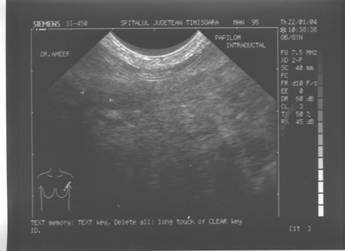

PAPILOM INTRADUCTAL